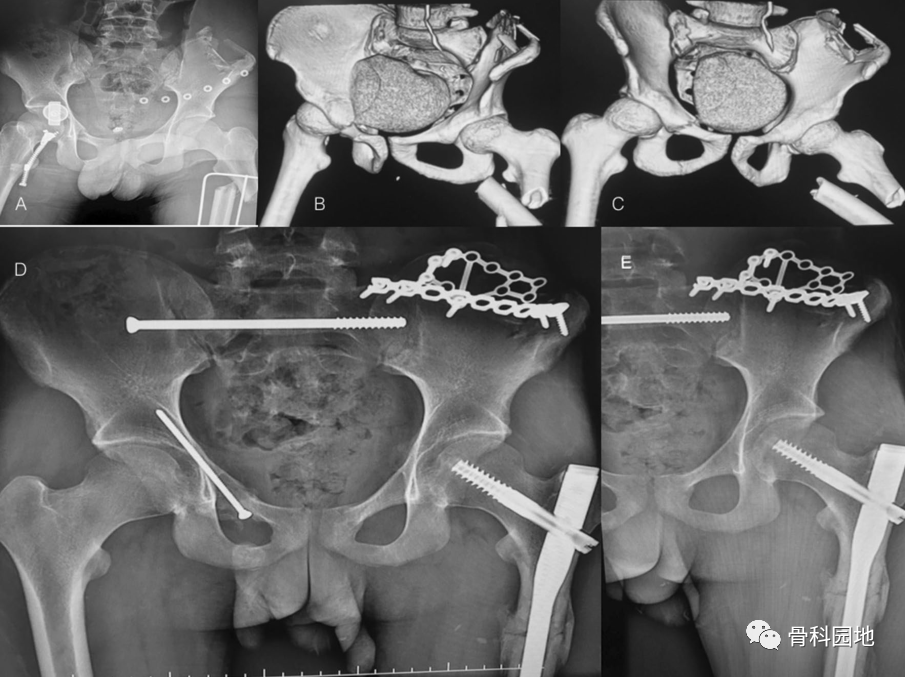

骨盆前后位 X 线片显示左侧股骨粗隆下骨折、右侧骶骨骨折、右侧耻骨支骨折和髂骨翼粉碎性骨折。左侧的跟骨板固定髂骨翼粉碎性骨折

二、髋臼四边体骨折

X线片显示左侧双柱髋臼骨折伴有四边体骨折移位。术后固定情况